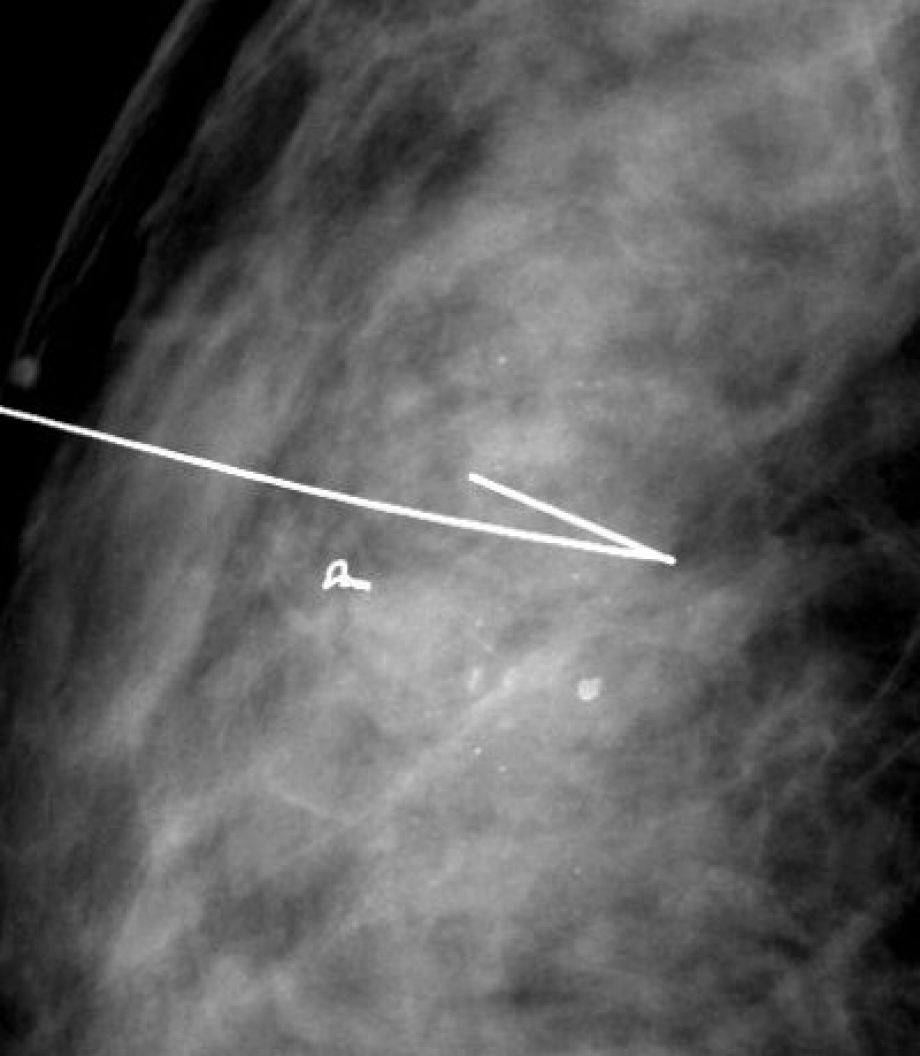

IRM, Scanner, radiographie, échographie, Doppler, Mammographie,Infiltration, Ponction et imagerie interventionnelle, Conebeam